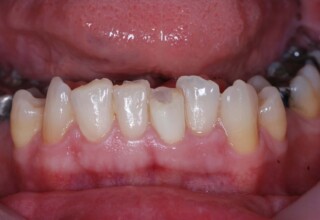

Dark root canal teeth

A rare case of dark root canal teeth with additional external absorption on the central incisor. After removal of the affected tissues of the central incisor, the tooth could not be directly bleached because of the soft tissue contact. The tooth was initially restored to provide the original tooth form, then it was bleached and the restoration was finalized.

Initial appearance

Final appearance